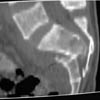

A 28 year old male jumped from the 4th floor on 11-25-2000 sustaining an L1 burst fracture that has been fixed anteriorly by the neurosurgeon with a strut between T12 and L2. A Kaneda device was placed anteriorly as well. My concern is the pelvic ring injury. There are bilateral sacral fractures through the foramen and a transverse element through the sacrum between S2 and S3. the lower part of the sacrum is displaced forward. Anteriorly there are right superior and inferior pubic rami fractures.

CT2